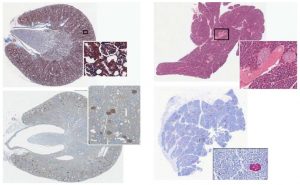

AngioMap is a Novel Image Analysis Algorithm for Assessment of Plasma Cell Distribution Within Bone Marrow Vascular Niche Abstract: The ability to characterize distribution of